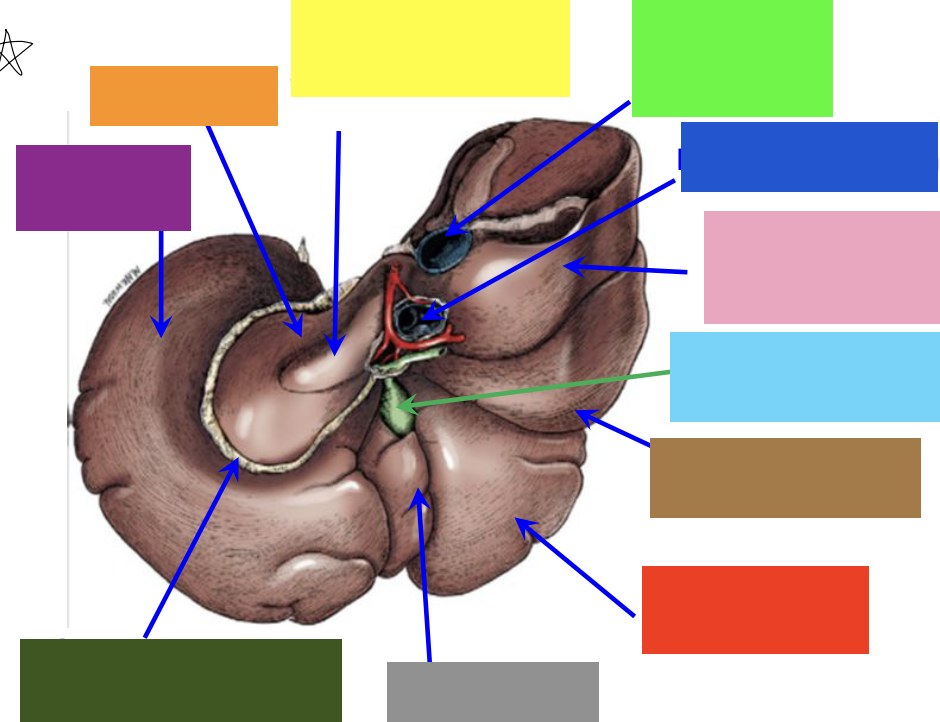

purple box

left lateral lobe

orange box

caudate lobe

yellow box

papillary process of the caudate lobe

neon green box

right lateral lobe

dark blue box

hepatic portal vein

pink box

caudate process of the caudate lobe

light blue box

gall bladder

brown box

right lateral lobe

red box

right medial lobe

grey box

quadrate lobe

dark green box

lesser omentum